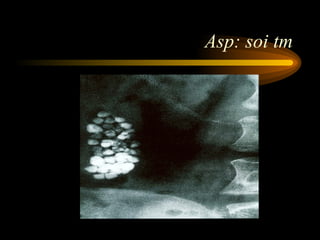

Asp: soi tm